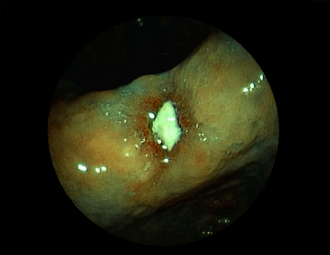

症例3:十二指腸潰瘍(53才男性)

1年前からの慢性胃痛を主訴に当院受診。十二指腸球部前壁に深くて大きな潰瘍(Stage A1)があり、潰瘍底は厚い白苔に覆われ、一部白苔のはみ出しを認める。潰瘍周囲粘膜は浮腫を伴っている。ボノプラザンフマル酸塩投薬で治療開始しました。

通常画像